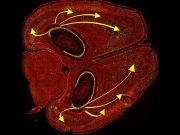

Biliminsanları farelerdeki özel anıları silmeyi başardı

Kaliforniya Üniversitesi’nde sinir bilimi ve psikoloji bilimi araştırmacıları, gerçekleştirdikleri deneyle ışığı farenin hafızasından belirli anıları silebilmek için kullandılar. Bu deneyle, beynin farklı noktalarının epizodik...